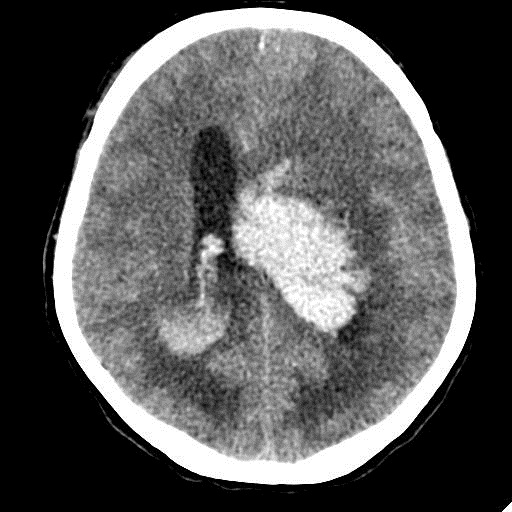

КТ головного мозга, кровоизлияние.

"Скорая" привезла женщину 75 лет, найденную на улице. На КТ направлена с д-зом: кома неясного происхождения. Вот такая картина на КТ.

Острое внутримозговое кровоизлияние с выходом крови в желудочки (боковые - сгустки преимущественно в левом + эффект седиментации с горизонтальным уровнем жидкость\жидкость в задних рогах; сгустки крови в третьем желудочке, кровь в четвертом). Значительное увеличение височных рогов боковых желудочков - гидроцефалия. Смешение срединных структур вправо, отек белого вещества перивентрикулярно слева.

Остается вопрос по слегка гиперденсному (относительно серго вещества) однородному фокусу в левой лобной доле... и по причине кровоизлияния. Что касается последнего могу предположить патологию базилярной артерии (разрыв аневризмы?)... правда не вижу что-то крови в цистернах основания черепа.

Я написала отек мозга, острое массивное (около 100 мл только внутримозговое) смешанное кровоизлияние слева + в стволе, с прорывом и гемотампонадой желудочков, выраженной латеральной дислокацией (13 мм), менингиома? лобного полюса слева. Убедительных данных за опухоль, давшую кровоизлияние, не вижу, хотя такая мысль тоже была.  Контрастировать такую пациентку никто не будет, агонизирующая(.

Тоже за менингиому, т.к. вижу широкое прилежание к серпу, неровные но четкие края образования и явное отграничение от ткани мозга, единичные кальцинаты, отсутствие воздействия на лобную кость.

У, сколько всего написано. Пока не пришла Nela, поучаствую и я. 1. Кровоизлияние в ткань мозга, а не в опухоль: а)не видно ткани опухоли; б) неясна первичная локализация опухоли (левые базальные ядра?!); в)нет перифокального отека вокруг предролагаемой опухоли, г) при опухолях прорывы в желудочки - редкость; 2) к поперечной дислокации добавил бы безесловную аксиальную: даже цистерна моста сужена, не говоря уже про обходную-четверохолмную и другие; 3) менингиома в левой лобной области, на мой взгляд, сомнительна (кстати, покажите ее пожалуйста), ИМХО - "игра" плотностей;  4) ///метастазы в сосудистые сплетения/// - это очень круто, но они не дали бы внутримозгового кровоизлияния, как и ///плексуспапилома///.

Массивное медиальное кровоизлияние с прорывом в желудочки. Кровоизлияние в ствол. Признаки вклинения. В лбу может что-то и есть, но это не принципиально. А может быть и отечные извилины. Смущает, что нет масс-эффекта.

Кровоизлияние не связанное с объемным образованием, "гипертоническое", основной массой - в области базальных ядер, кровоизлияние в ствол мозга, кома ясного происхождения :) А менингиома менигниомой, не мешает, так сказать.  Отека мозга здесь небольшой, больше выражено набухание.